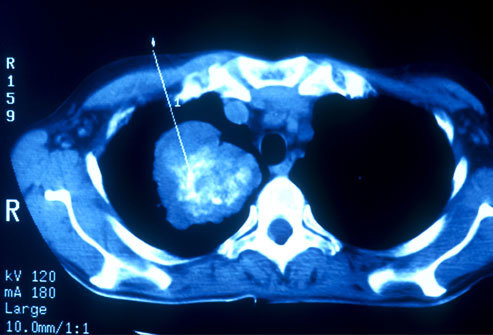

Sàng lọc ung thư phổi

Ung thư phổi có thể được phát hiện sớm bằng chụp CT. Ở Mỹ, có một số đối tượng được khuyên đi sàng lọc ung thư phổi như những người hút thuốc hay có người thân nghiện thuốc, sống trong môi trường ô nhiễm, những người từ 55 đến 80 tuổi được khuyến cáo đi sàng lọc ung thư phổi. Nếu bệnh nhân có tiền sử hút thuốc lá nên định kỳ đi kiểm tra sức khỏe phổi. Ở những người trẻ nếu dừng hút thuốc trong vòng 15 năm có thể ngừng khám sàng lọc ung thư phổi.